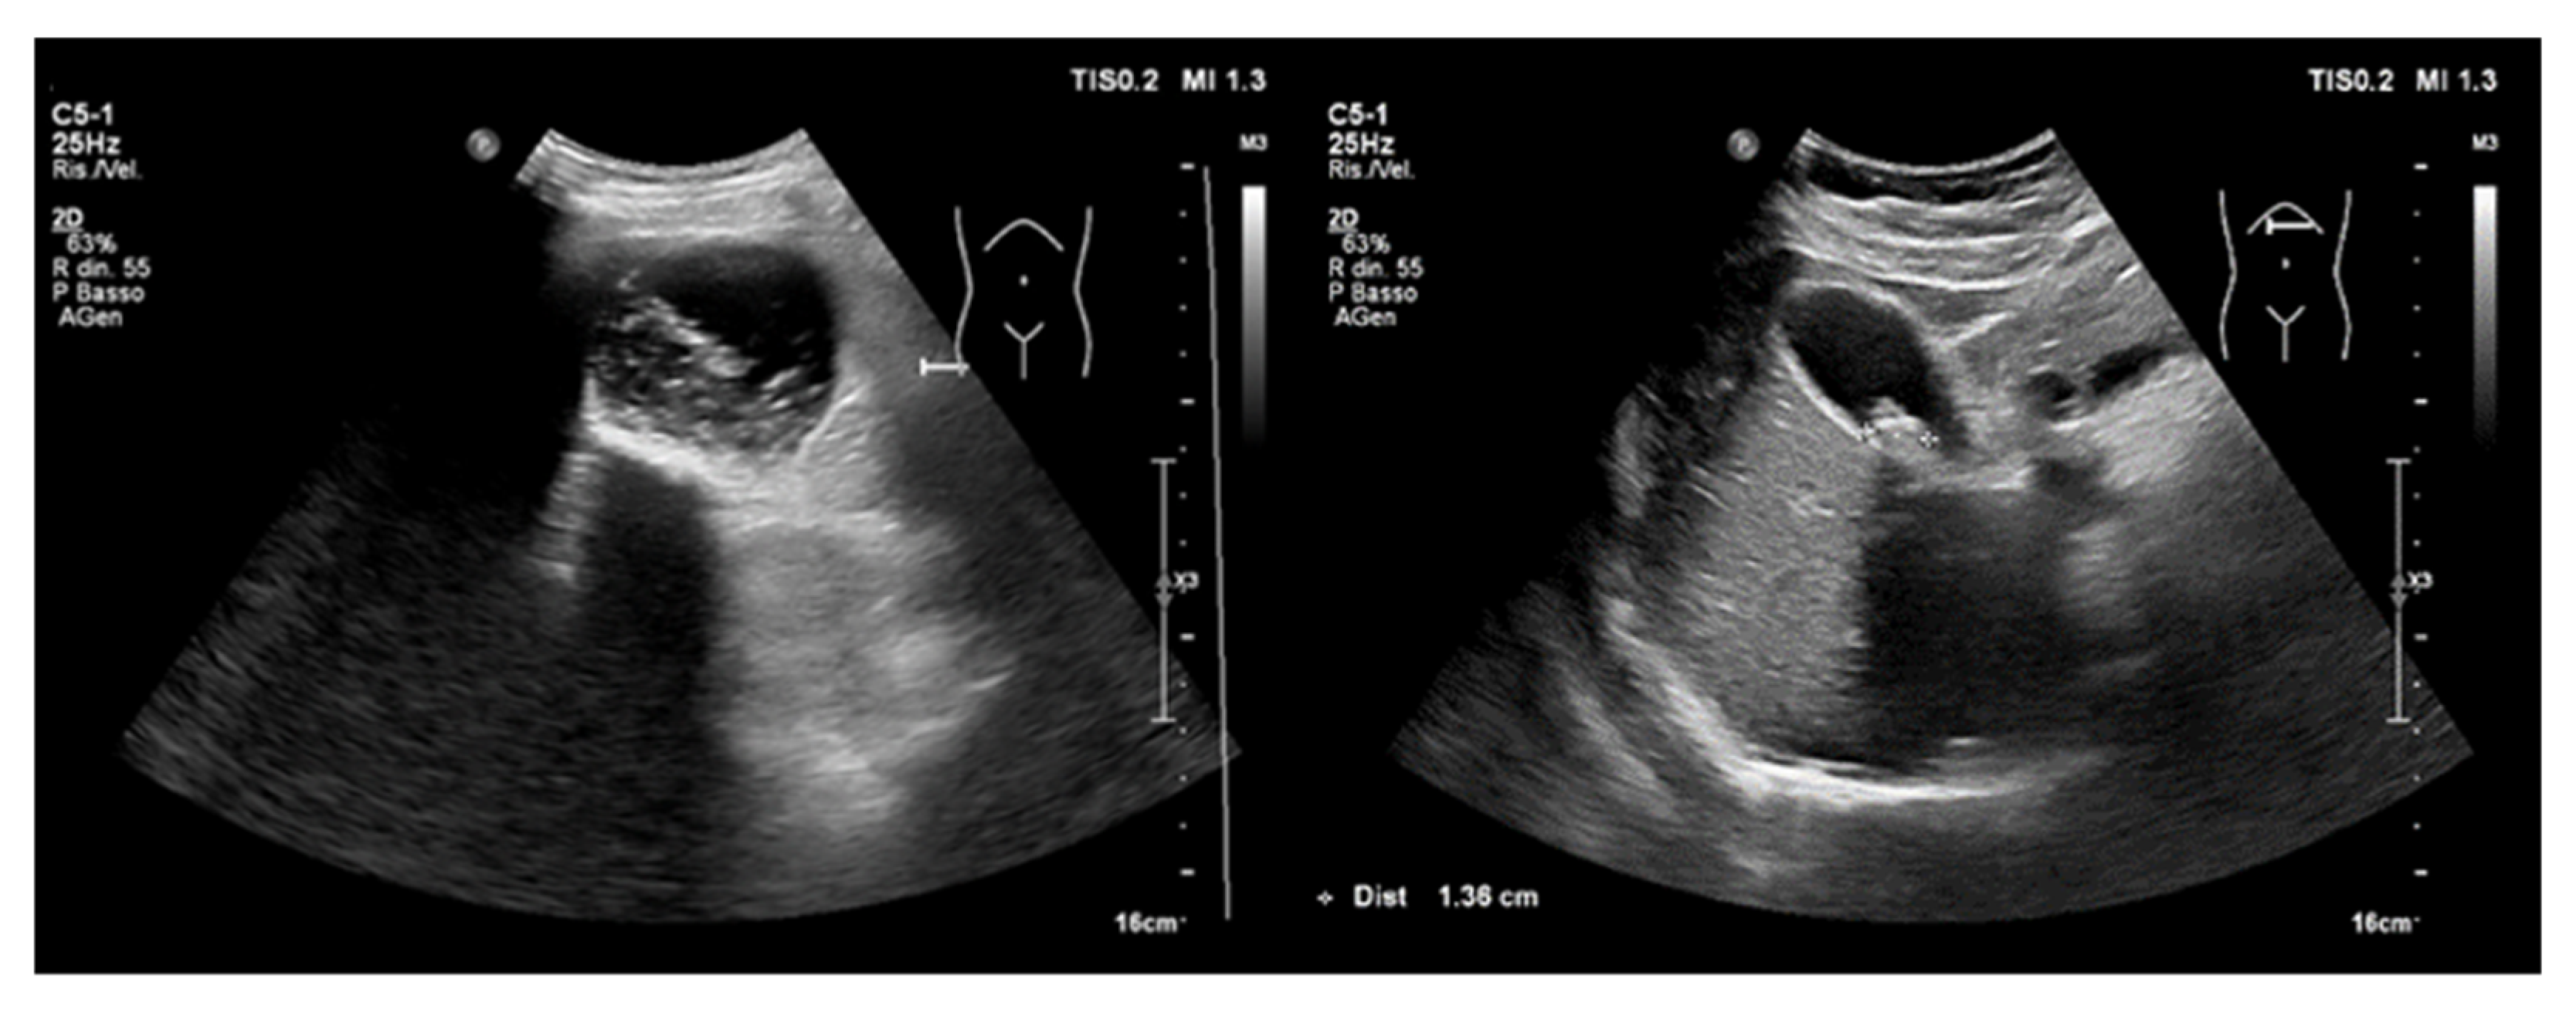

4. Point-of-Care Abdominal Ultrasound

4.1. Acute Abdominal Pain

- Appendicitis and Cholecystitis

- Abdominal aortic aneurysm

4.2. Acute Kidney Injury

4.2.2. Obstructive AKI